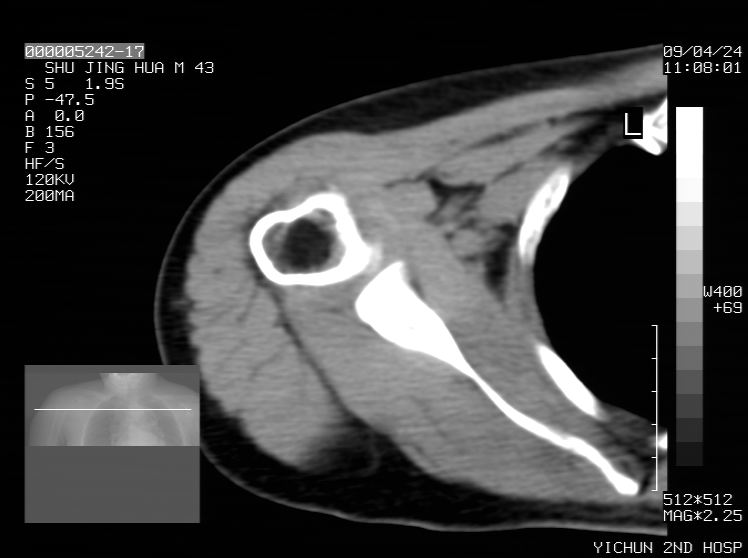

标题: CT19569:请会诊,女50岁,右肩疼痛数月 [打印本页]

标题: CT19569:请会诊,女50岁,右肩疼痛数月

骨软骨瘤?

考虑骨软骨瘤可能

剥脱性骨软骨炎

钙化性肌腱炎

是指钙盐沉积在变性肌腱中的一种无菌性炎症,常见于肩关节的肩袖肌腱,引起肩部疼痛和活动受限。分为急性和慢性两种类型,急性型有肩关节突然出现急性疼痛的发作史,夜间可痛醒。